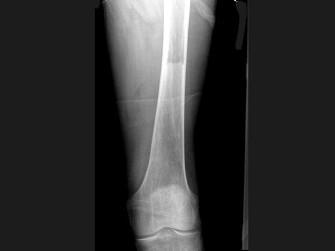

问题 男,60岁,左股骨痛1年余,结合图像,最可能的诊断是?(?)

选项 A.骨纤维异常增殖症 B.Paget病 C.髋关节结核 D.股骨头缺血坏死 E.化脓性骨髓炎

答案 B